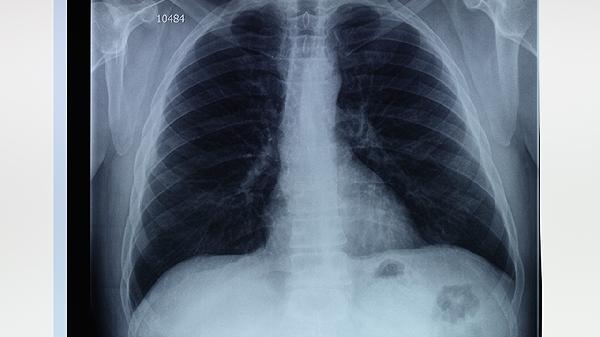

肺大泡怎样治疗

肺大泡的治疗方法包括药物治疗、手术治疗和生活方式调整,具体选择取决于病情严重程度。药物治疗如抗生素、支气管扩张剂和糖皮质激素可缓解症状;手术治疗如肺大泡切除术、肺减容术和肺移植适用于严重病例;生活方式调整如戒烟、适度运动和保持健康体重有助于改善肺功能。